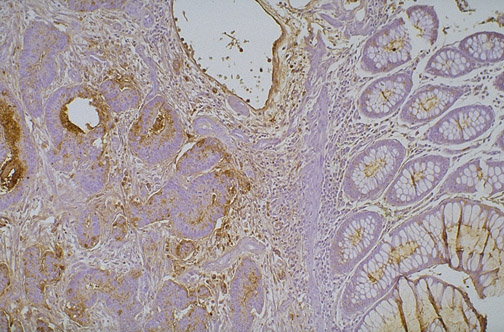

Carcinoembryonic antigen (CEA) positivity is marked in the neoplastic cells of the adenocarcinoma at the left, below the remaining normal colonic mucosa at the right, which has normal cells expressing little CEA.